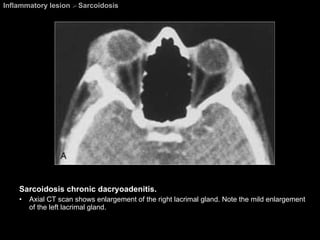

Sarcoidosis A granulomatous systemic disease. Pathology = Noncaseating granulomas  Diagnosis based on biosy. Affecting all races, both sexes, and all ages.  Presentation : asymptomatic with abnormal findings on CXR.   Visual system abnormalities  are the most common extrathoracic manifestations of sarcoidosis.

Sarcoidosis Ophthalmic lesions develop in approximately 25% of patients. Chest abnormalities are found in about 80% of patients with ocular sarcoidosis. Any part of the globe or orbit may be involved.  M/c orbital involvement  =  chronic dacryoadenitis .  May be unilateral and easily mimic a lacrimal gland tumor.

Sarcoidosis A Mikulicz-like syndrome  =  Sacoidosis involvement of bilateral lacrimal glands and salivary gland causings dry eyes and xerostomia. The most common cranial nerves to be affected are the  CN 2 , 7, 5, 8, 3, 6 respectively.

Inflammatory lesion  >  Sarcoidosis Sarcoidosis chronic dacryoadenitis.  Axial CT scan shows enlargement of the right lacrimal gland. Note the mild enlargement of the left lacrimal gland.